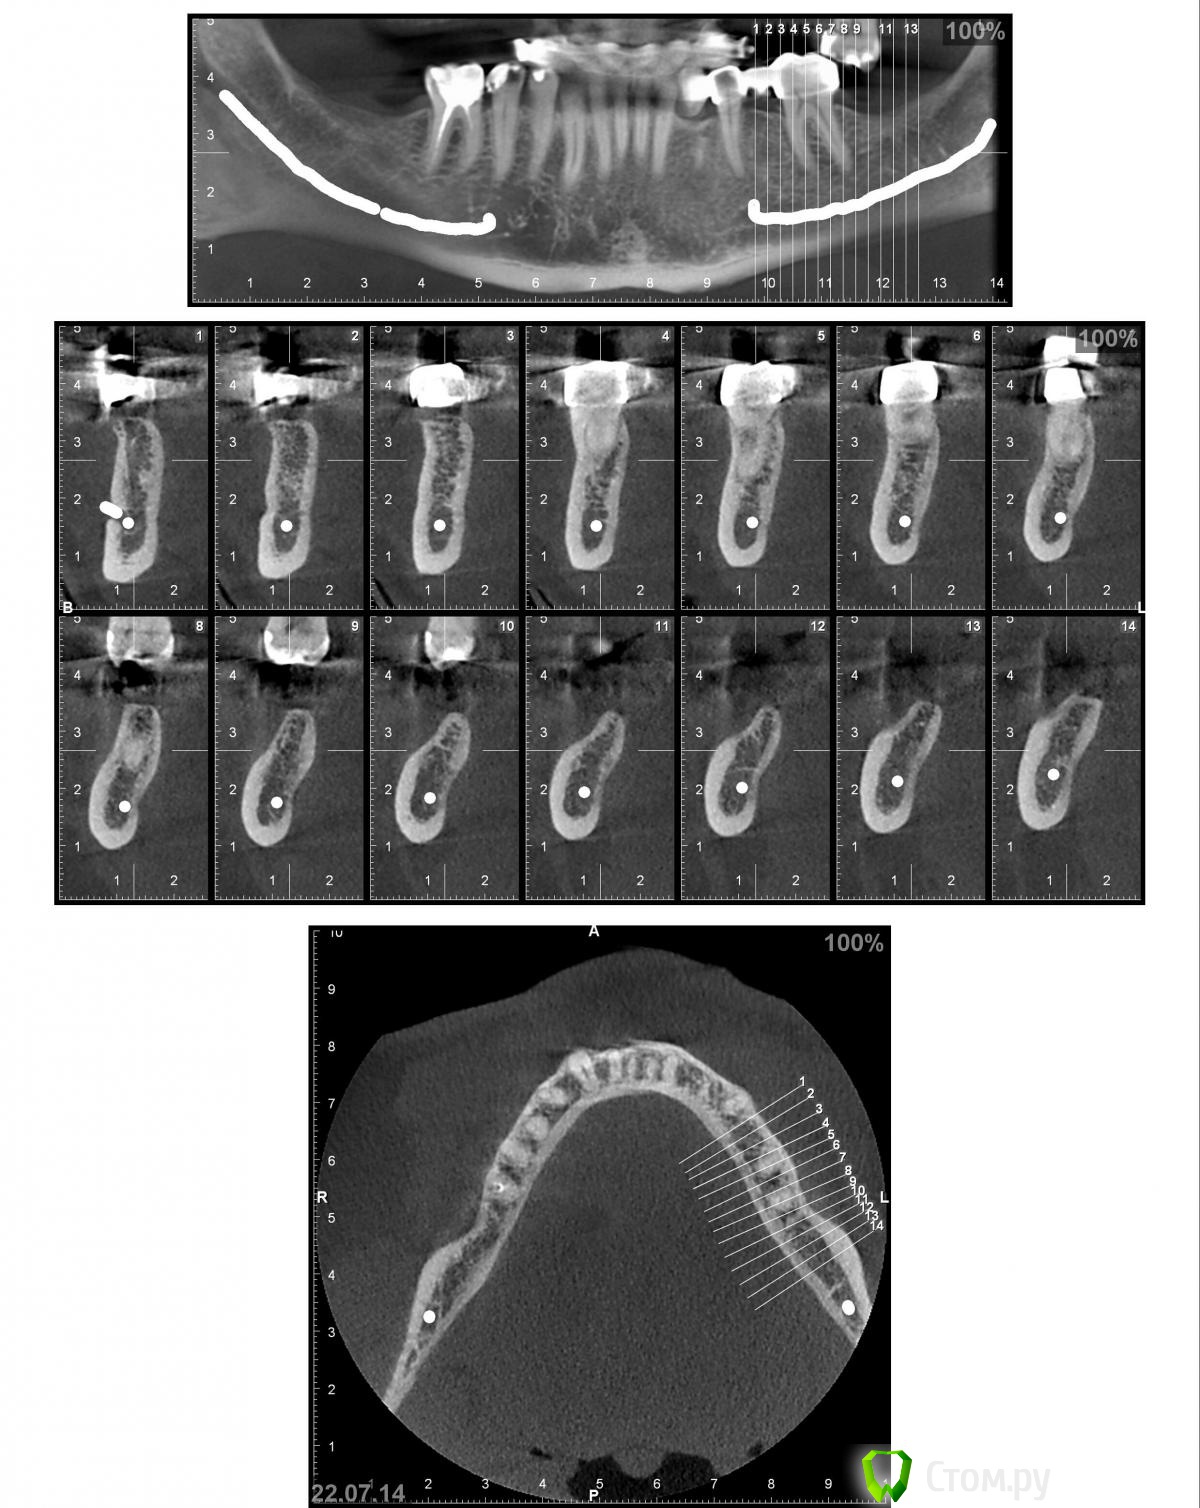

Nadeghda Опубликовано 13 октября, 2014 Поделиться Опубликовано 13 октября, 2014 Доброго времени суток, коллеги!Хотела узнать мнения относительно вариантов протезирования в/ч пациента.После консультации ЛОР - врача от оперативных вмешательств на ППН отказался. 13 и 23 удалены, лунки затягиваются. Варианты:1) имплантаты 13,15,23,25- мостовидные конструкции2) имплантаты 13.23; 15 и 25 - под углом 35'(ski)- локаторы- съемный протез3) имплантаты 13,23; 15,25- под углом 35' - мостовидные протезыМожет еще кто-нибудь что-либо предложит?Заранее спасибо! Ссылка на комментарий

Дмитрий Никитюк Опубликовано 14 октября, 2014 Поделиться Опубликовано 14 октября, 2014 Спасибо большое, что не оставили мой вопрос без внимания и за пояснение тоже)))Не за что. Ставьте в области клыков и вторых премоляров под углом, и смело цепляйте консоли. Когда умрут резцы, будет отлична конструкция "всё на 6". Ссылка на комментарий